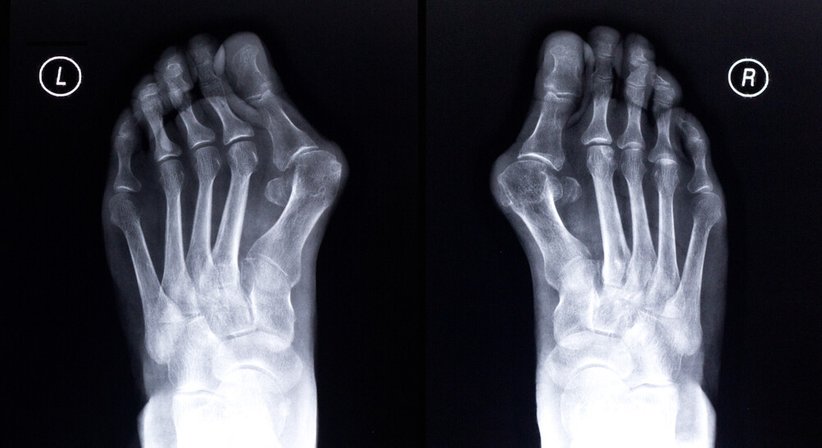

Der Hallux valgus, die häufigste Fehlstellung des vorderen Fußes,

stellt zu Beginn meistens nur ein ästhetisches Problem dar, führt im weiteren Verlauf jedoch häufig zu starken Schmerzen und anderen Beschwerden.

Es handelt sich um eine Fehlstellung der Großzehe, bei welcher diese von ihrer ursprünglichen Position abweicht - das Grundgelenk der Großzehe schiebt sich allmählich nach außen, wobei sich eine für den Hallux valgus charakteristische Wölbung bildet.

Durch die "Verdrehung" der Großzehe werden auch die kleineren Zehen zusammengedrückt; sie weichen aus, was wiederum die Entstehung anderer Fehlstellungen (Krallen- und Hammerzehen) begünstigt.